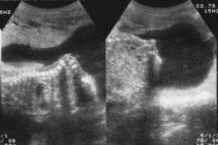

3. Diastématomyélie :

Fait partie des spina bifida occulta.

Correspond à une pision sagittale, non totale de la moelle, en deux cordons séparés ou non par un septum osseux ou cartilagineux, septum en continuité avec la partie dorsale du corps vertébral et/ou la partie ventrale de l'arc postérieur.

Les deux cordons médullaires se rejoignent pour former le cône terminal en général unique.

Association fréquente avec anomalies du développement des vertèbres : Diminution de leur diamètre antéro-postérieur, hémivertèbre, bloc vertébral.

Revêtement cutané intact. Parfois dysraphie spinale ouverte.

En échographie : Cloison échogène entre les points d'ossification postérieurs de la vertèbre. "Troisième point d'ossification postérieur" avec lames latérales anormalement écartées.